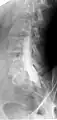

Myelogram showing arachnoiditis in the lumbar spine.

Myelography is a type of radiographic examination that uses a contrast medium to detect pathology of the spinal cord, including the location of a spinal cord injury, cysts, and tumors. Historically the procedure involved the injection of a radiocontrast agent into the cervical or lumbar spine, followed by several X-ray projections. Today, myelography has largely been replaced by the use of MRI scans, although the technique is still sometimes used under certain circumstances – though now usually in conjunction with CT rather than X-ray projections.